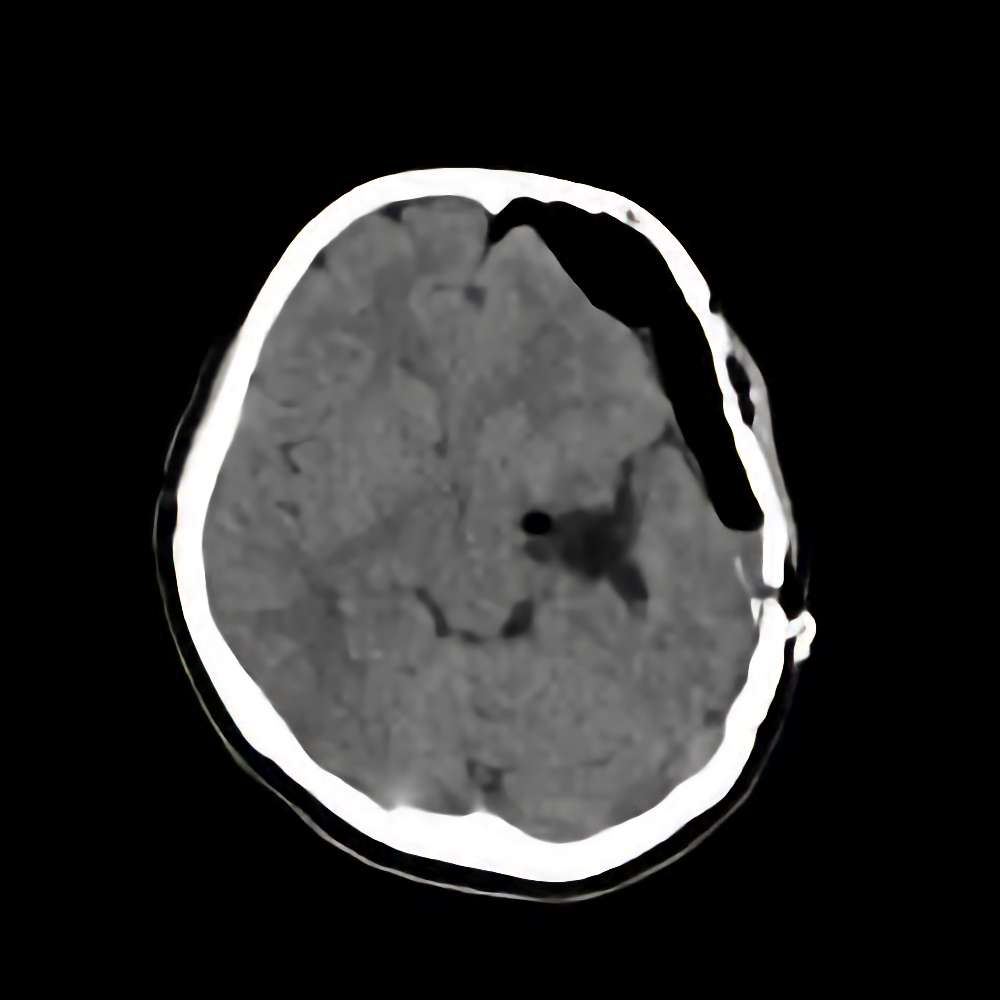

症例 '16年2月

No.

※ 画像をクリックすると拡大表示します。症例No.は平成29年から起算しています。

年_番号

手術年月

患者年齢

’16_17

'16年2月

10代

病名

術式

備考

海綿状血管腫

断層撮影

手術前